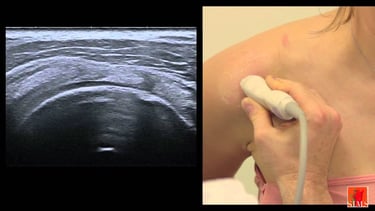

Pathologie de la coiffe des rotateurs

L'épaule et le genou sont deux articulations ou l'on réalise énormément d'arthroscopie, technique mini-invasive sous caméra.